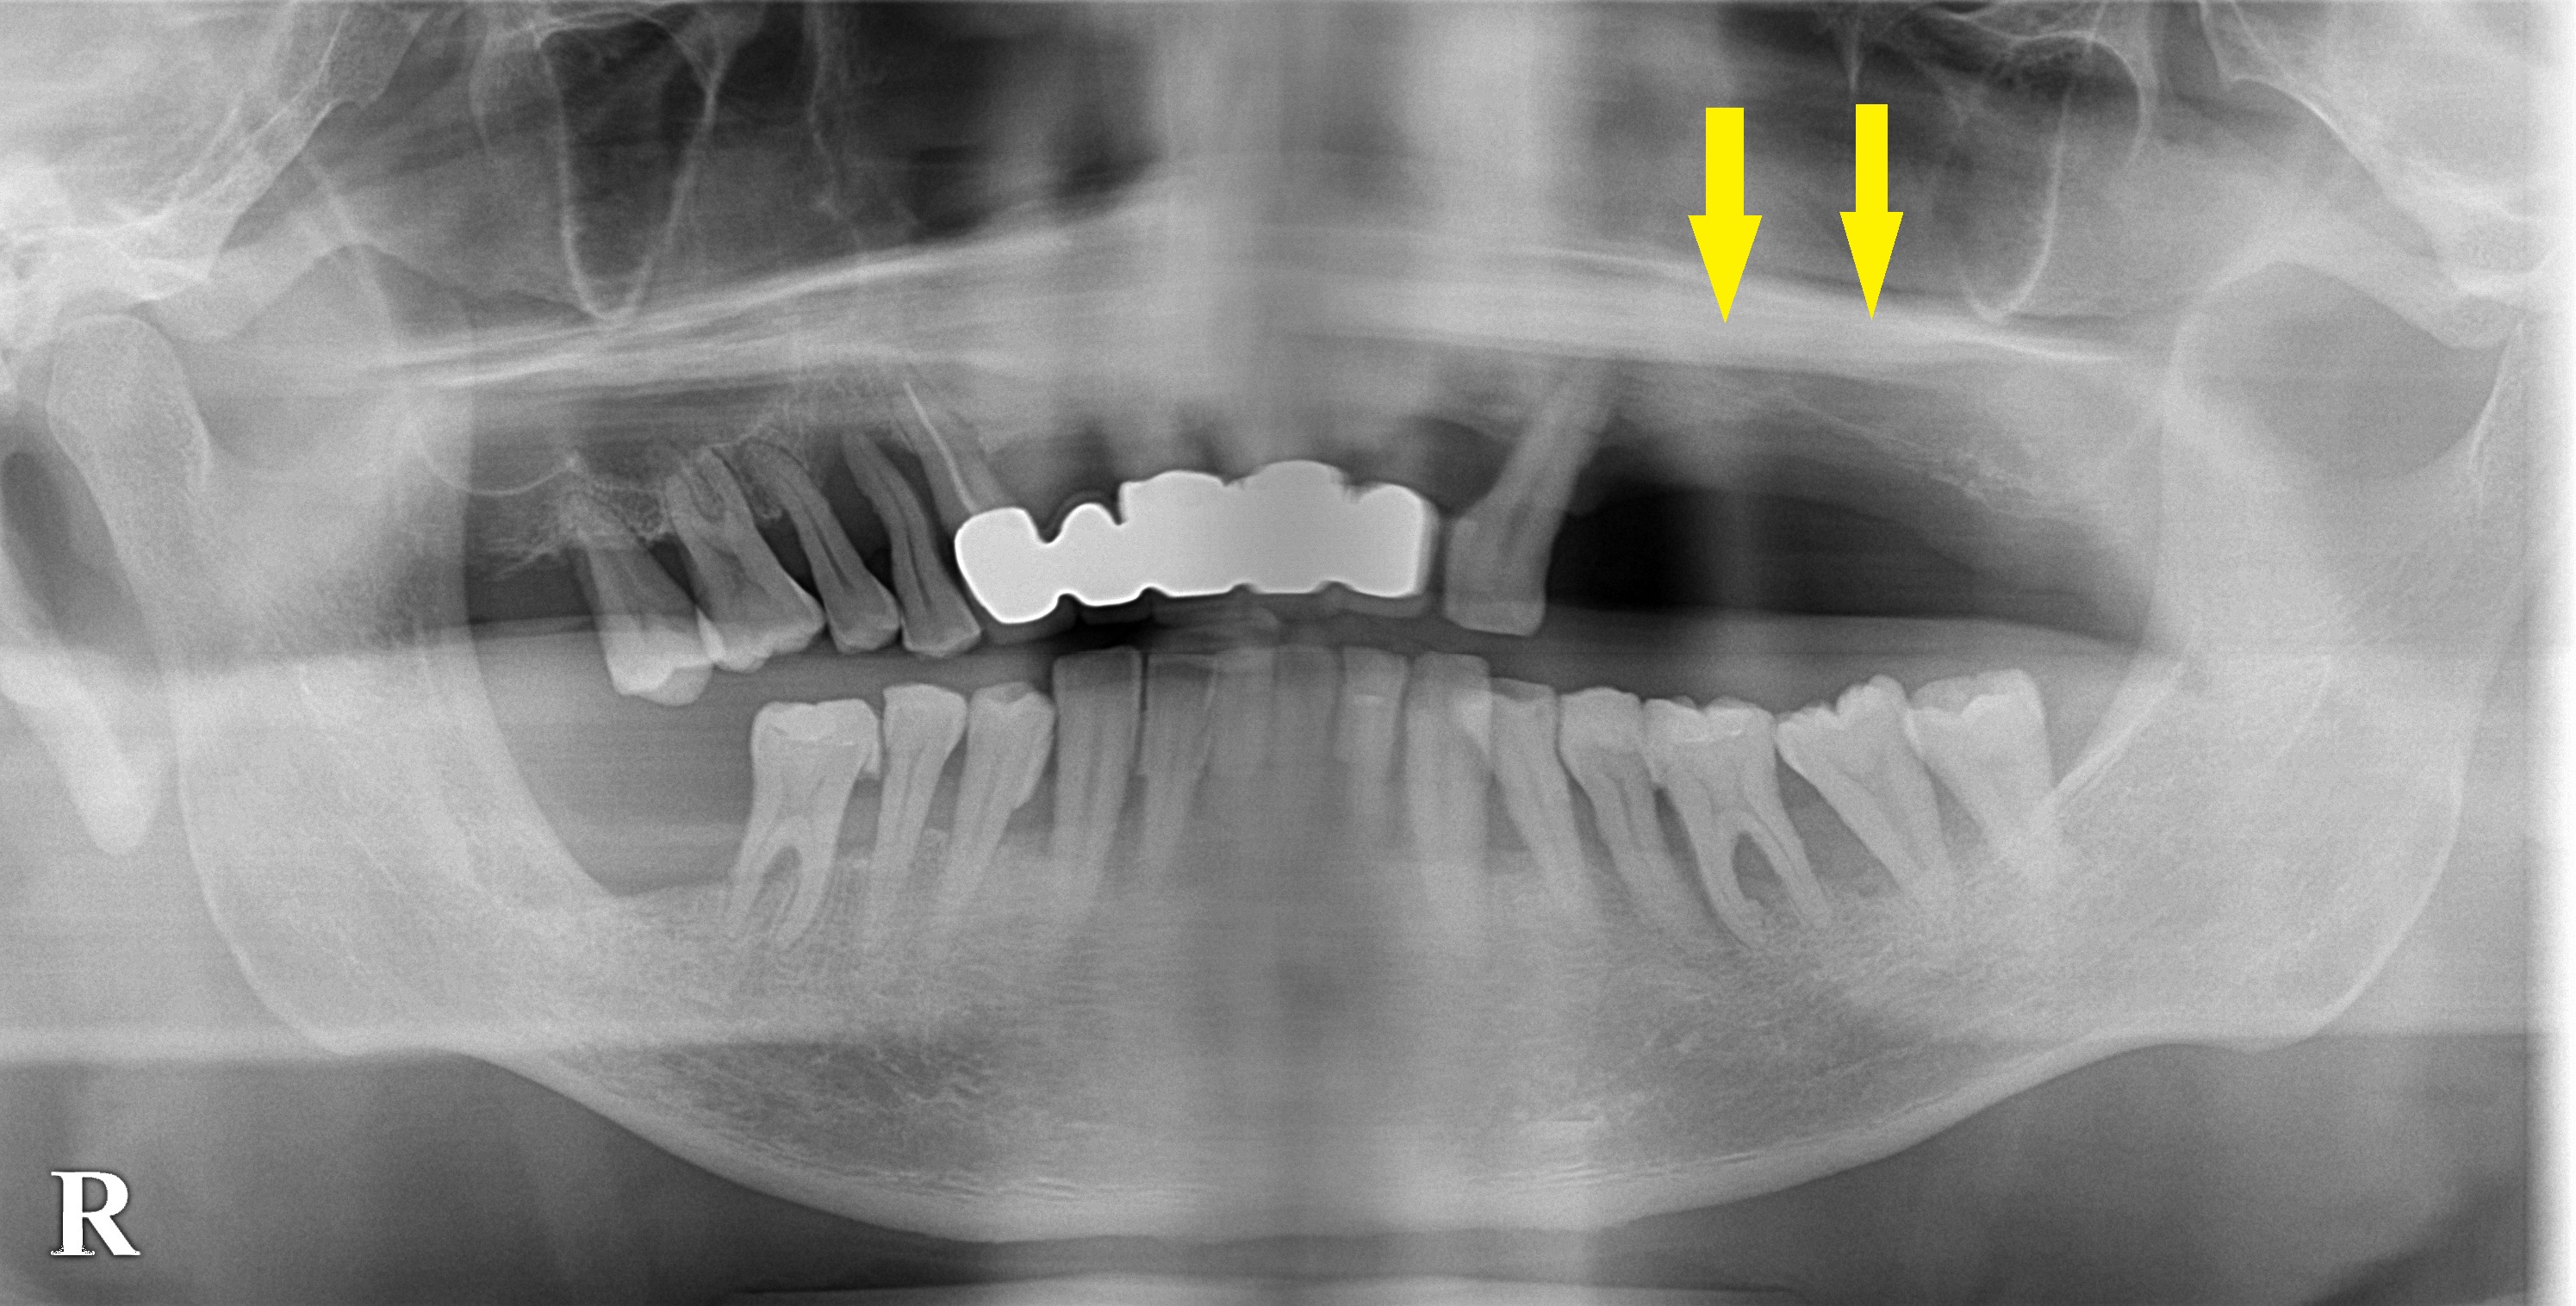

レントゲン写真で、確かに、左上顎臼歯部は骨が少なく一部は紙のように薄いところもありました。

サイナスリフトという方法で骨を増やし、インプラント埋入を可能にできることを説明させていただきました。